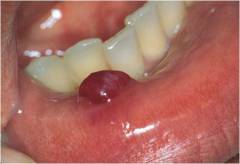

Подобные кисты могут образовываться в любой железе по всему организму: яичников, подъязычных слюнных желез, верхней и нижней губ, шейки матки, миндалин, легких, печени и так далее.

Фото: так выглядят симптомы ретенционной кисты нижней губы.